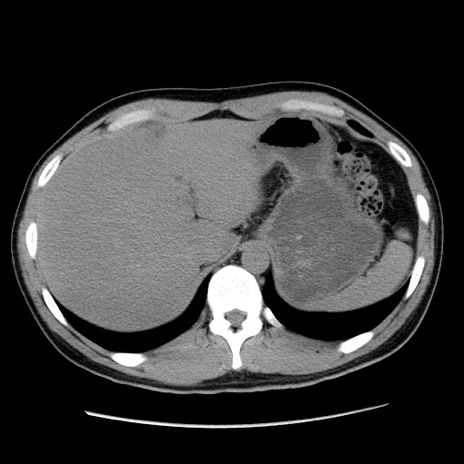

症例36(横断像)

【症例】20歳代 男性

【主訴】心窩部痛

【現病歴】今朝より上腹部痛あり。一旦軽快していたが再度出現したため救急要請。昨日夕に白身の魚を含む刺身を食べた。

【身体所見】BP 136/89mmHg、HR 74/min、BT 37.0℃、腹部:膨満、軟、心窩部に圧痛あり。反跳痛なし、筋性防御なし、腸雑音やや亢進あり。

【データ】WBC 17700、CRP 0.48